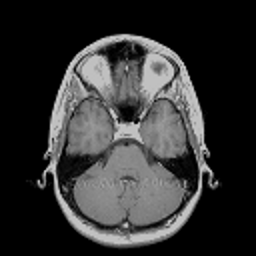

VII-C Experiments with real-life data

Reconstruction of real-life MRI images has been the next step in our comparative study. To this end, the data set of [19] have been used herein. The data were obtained at the University Hospital of Ghent and it is publicly available at http://telin.ugent.be/~sanja/Sanja_files/Software/MRIprogram.zip. The data contains a sagittal and an axial scan of a human brain, which are shown in Fig. 10 and Fig. 11, respectively.

The reconstruction results obtained for each of the tested images using the proposed and reference methods are shown in Subplots (b)-(f) of Fig. 10 and Fig. 11, respectively. From these figures, it can be seen that the proposed algorithms result in higher-contrast reconstructions of better visual clarity as compared to the reference approaches. The difference is particularly evident for the case of Fig. 11, where the proposed algorithms result in less noisy images, while exhibiting higher effective resolution and contrast.

Figure 10: (a) Sagittal MRI scan; (b)-(f) Reconstruction results obtained using TVDN, WDN, GNLM, NLMS and NLMR, respectively.

Refer to caption

Figure 11: (a) Axial MRI scan; (b)-(f) Reconstruction results obtained using TVDN, WDN, GNLM, NLMS and NLMR, respectively.